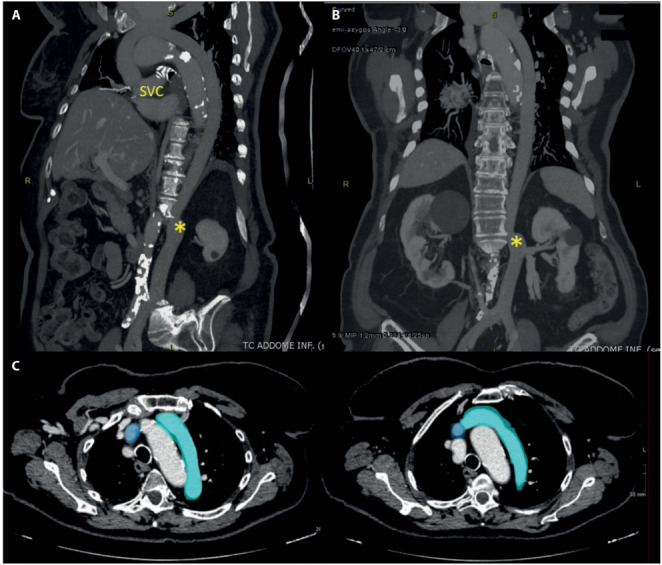

下腔静脉(IVC)中断伴奇静脉/半奇静脉延续是一种极不常见的先天性血管异常,可能存在多种变异。因此,在文献中找到相同的解剖学变体是具有挑战性的。我们报告了一例83岁女性患者的IVC中断伴半奇果和经肝持续的独特病例。该病例通过计算机断层扫描(CT)作为成像模式进行评估,采用多阶段方案,能够准确检测这种复杂的血管异常。本病例报告的目的不仅是介绍这一引人注目的病例,而且从IVC和奇静脉系统的解剖学和胚胎学出发,简要介绍IVC中断的类型,并讨论成像在检测血管异常中的价值。

Inferior vena cava (IVC) interruption with azygos/hemiazygos continuation is an extremely uncommon congenital vascular anomaly, which may present with multiple variants. As a result, it is challenging to find in the literature the same anatomical variant. We report a unique case of an interrupted IVC with hemiazygos and transhepatic continuation in an 83-year-old female patient. The case was evaluated by performing Computed Tomography (CT) as imaging modality, with a multiphase protocol, able to detect accurately this complex vascular anomaly. The purpose of this case report is not only to present this remarkable case but also to briefly show the types of interrupted IVC, starting from the anatomy and the embryology of the IVC and the azygos system, and to discuss the value of imaging in detecting the vascular anomaly.